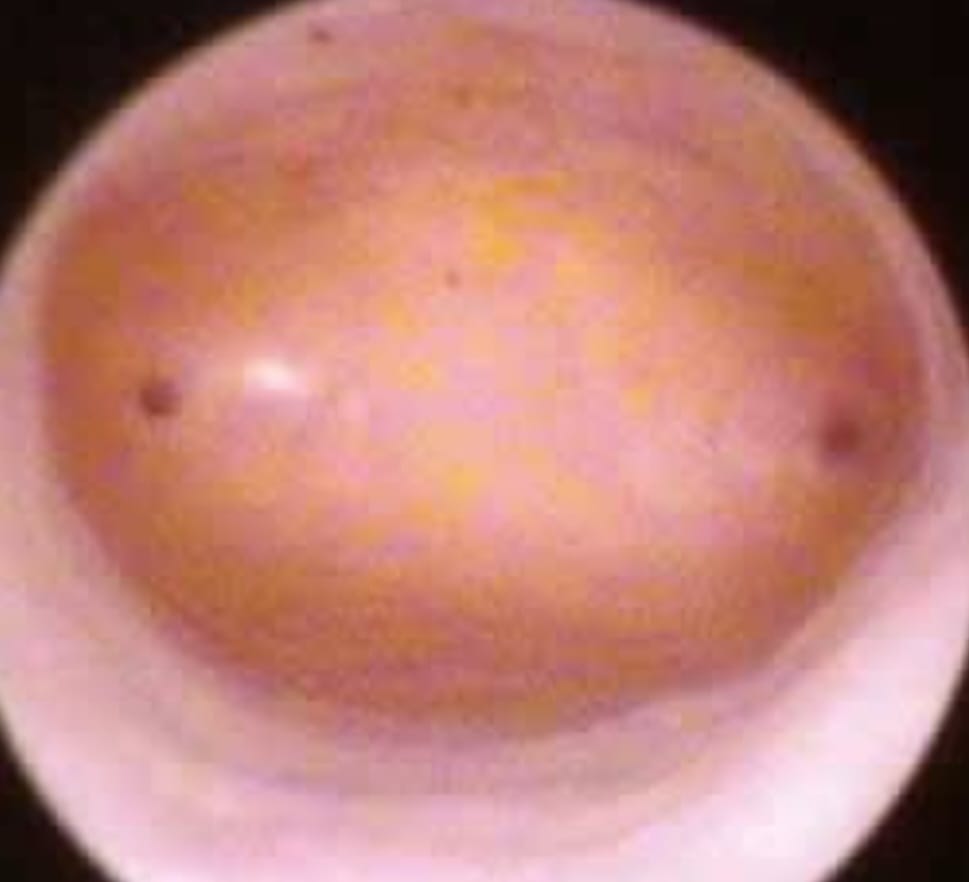

Hysteroscopy is a minimally invasive procedure used to diagnose and treat uterine conditions. It involves inserting a thin, lighted instrument called a hysteroscope through the cervix to examine the uterus, helping identify issues like fibroids, polyps, adhesions, abnormal bleeding, or infertility-related concerns. This procedure is performed on an outpatient basis, requires no major incisions, and allows for quick recovery with minimal discomfort. Hysteroscopy is often used for both diagnostic and operative purposes, making it an essential tool in advanced gynecological care. Get precise diagnosis and treatment with hysteroscopy – Book your appointment today.